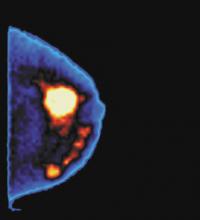

Broadwest's software-only solution (in partnership with InsightMRI) for interpreting Breast MR features tools to discern enhanced blood flow associated with tumors in a kinetic manner, enhanced visualization of small lesion morphology, and provides parametric maps and patented blink technology for comparisons of pre- and post-contrast images and use on existing PCs.